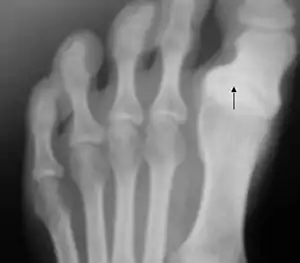

| Radiography of the left foot of a young male showing progressive hallux varus | |